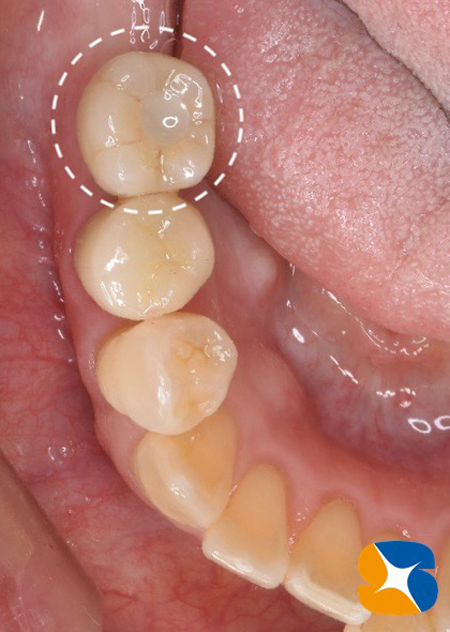

施術より3ヶ月後、インプラント完成。

施術から3ヶ月後、インプラント完成。

適合の良くなかった前歯もセレックを使って、オールセラミックスに順次やり変え。